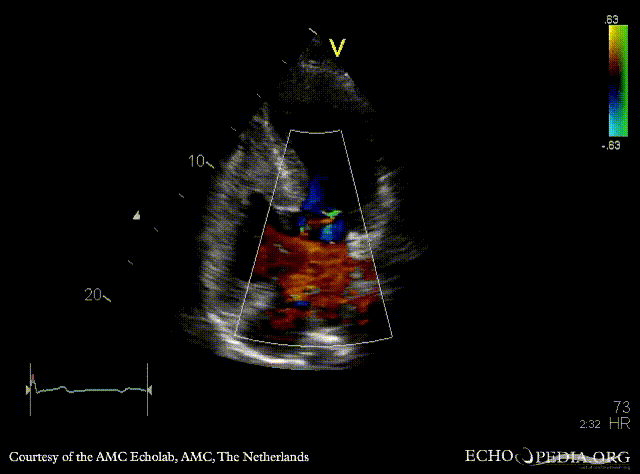

A4CH: color Doppler of AV valve regurgitation